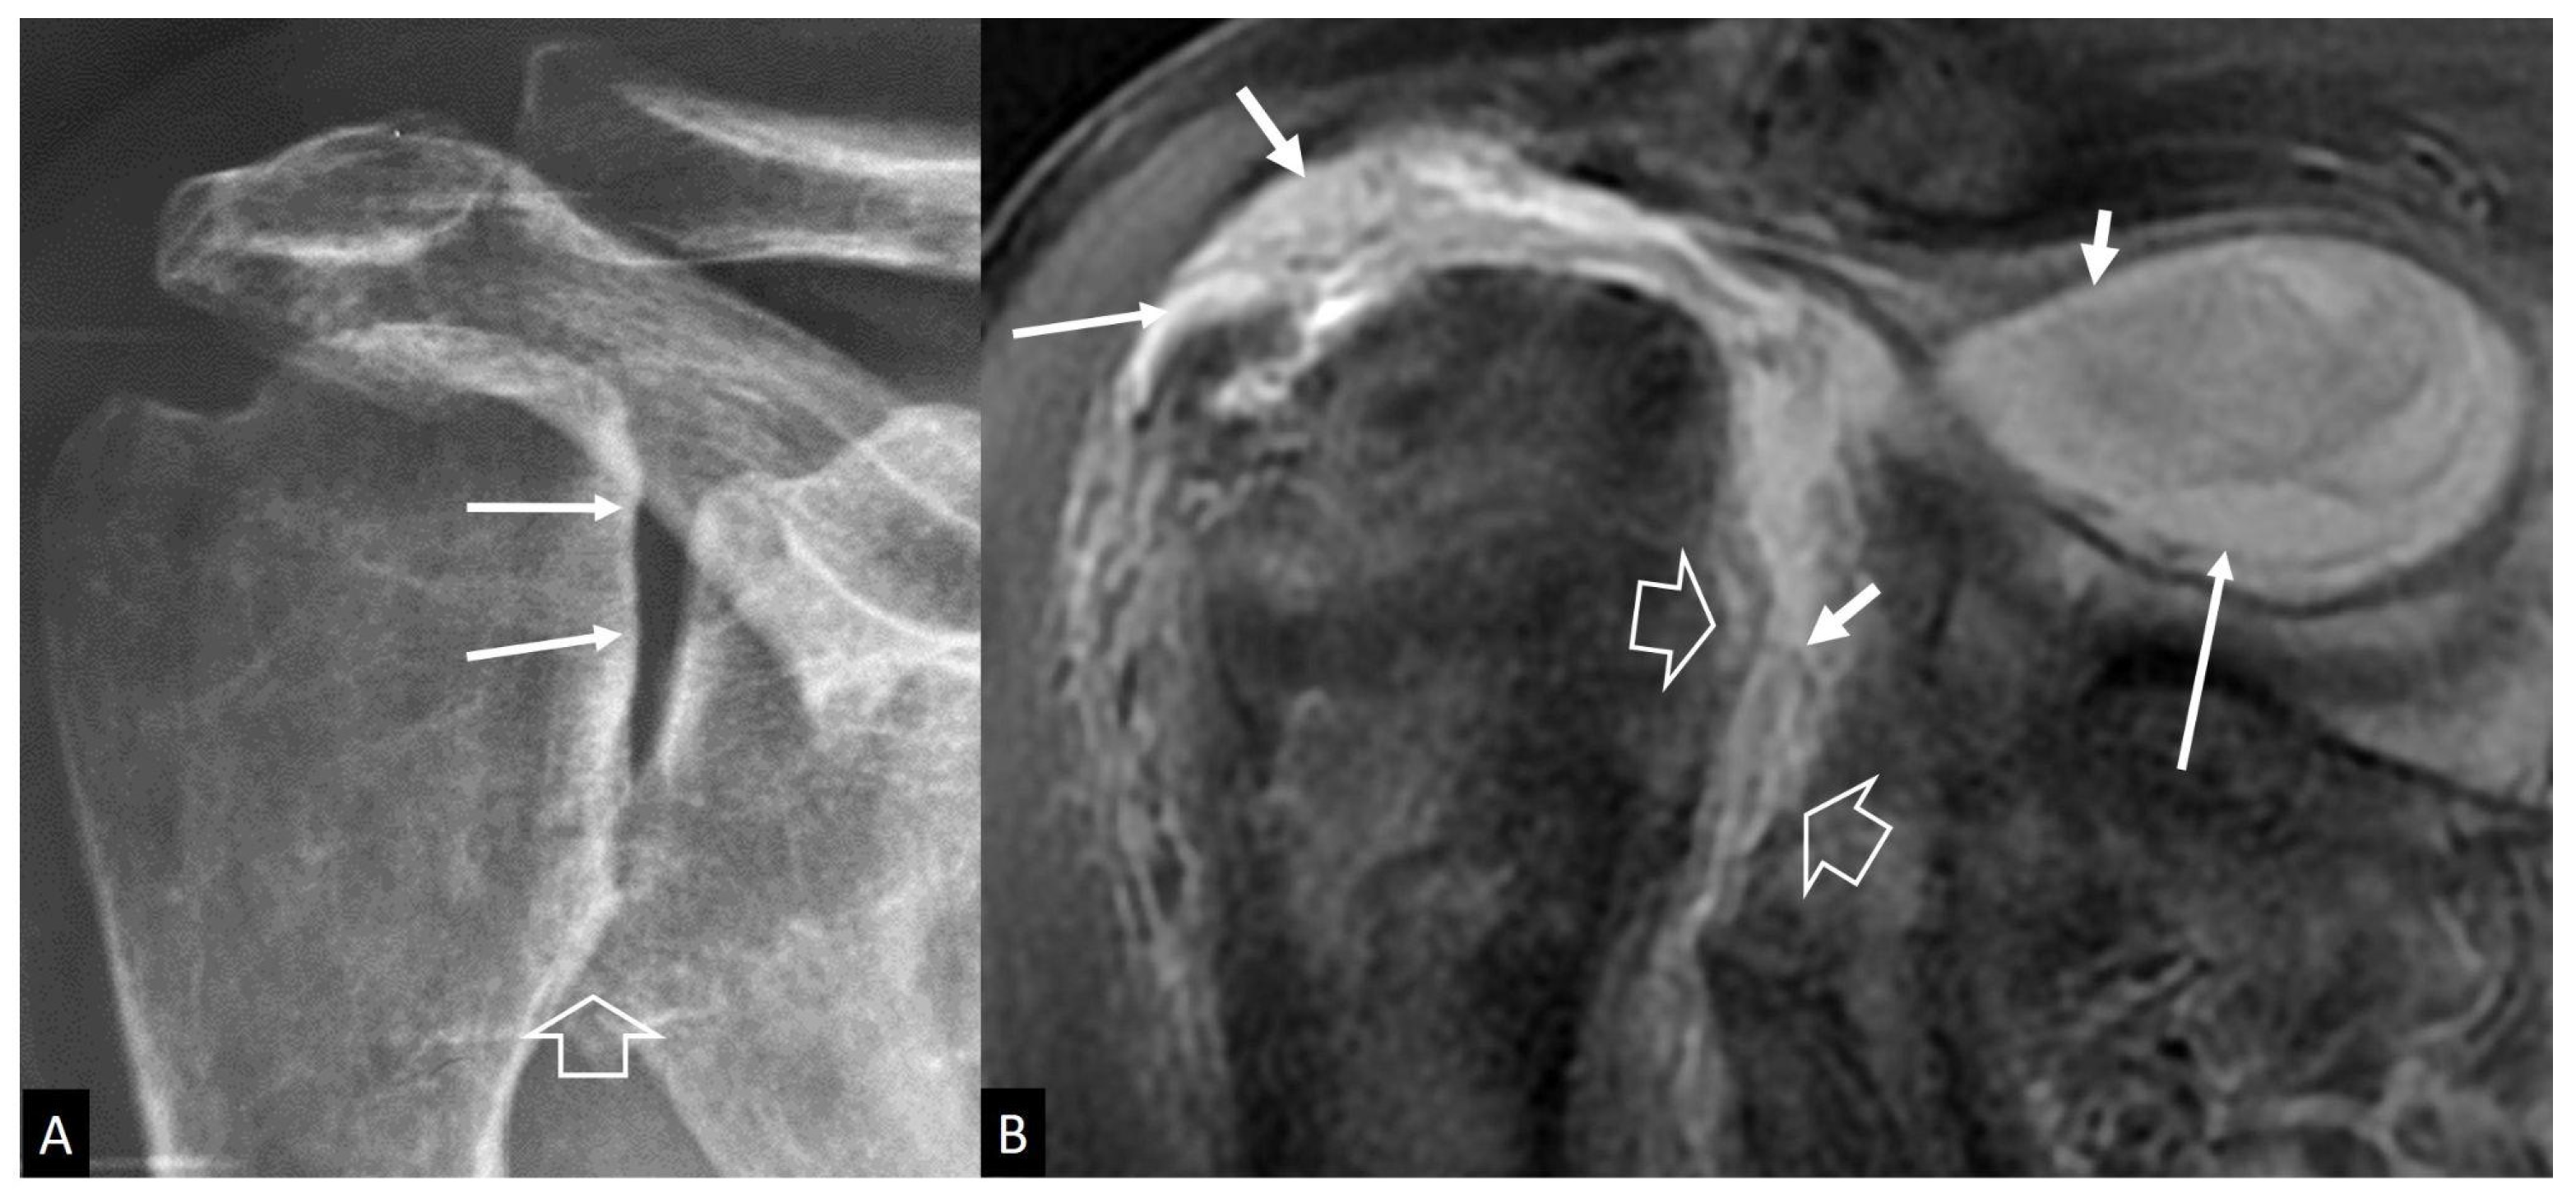

4.2.4. Rapidly Destructive Osteoarthritis of the Hip

- Flemming, D.J.; Gustas-French, C.N. Rapidly progressive osteoarthritis: A Review of the clinical and radiologic presentation. Curr. Rheumatol. Rep. 2017, 19, 42. [Google Scholar] [CrossRef] [PubMed]

- Boutry, N.; Paul, C.; Leroy, X.; Fredoux, D.; Migaud, H.; Cotton, A. Rapidly destructive osteoarthritis of the hip: MR imaging findings. AJR Am. J. Roentgenol. 2002, 179, 657–663. [Google Scholar] [CrossRef] [PubMed]

- Zazgyva, A.; Gurzu, S.; Gergely, I.; Jung, I.; Roman, C.O.; Pop, T.S. Clinico-radiological diagnosis and grading of rapidly progressive osteoarthritis of the hip. Medicine 2017, 96, e6395. [Google Scholar] [CrossRef] [PubMed]